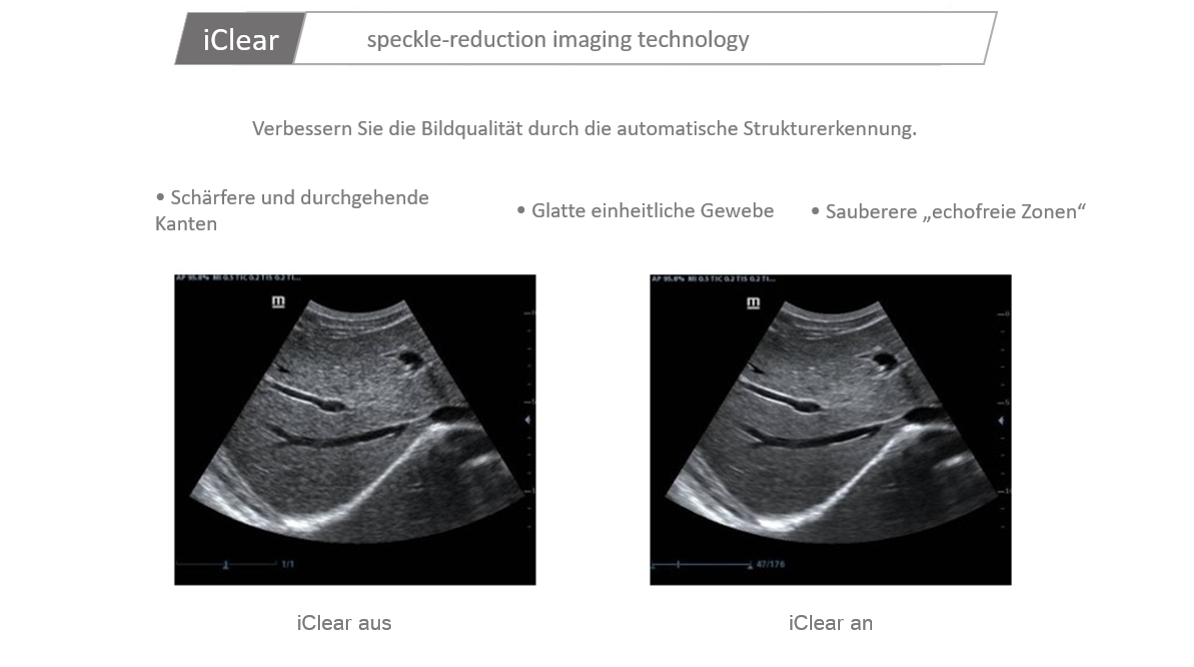

Der Einsatz anerkannter Bildgebungstechnologien macht das DC-30 mit Full HD sehr leistungsstark und hochwertig. Sie sind erfolgreich aus etablierten Ultraschallsystemen migriert worden. Eine clevere Kombination von Ultraschallsonden mit spezialisierten Schallk?pfen unterstĂŒtzt erstklassige Ergebnisse in einem breiten Anwendungsspektrum. Mit Hilfe der Breitband-Schallk?pfe l?sst sich eine Vielzahl an Patiententypen erfolgreich untersuchen. Diese bew?hrten Ultraschalltechnologien sorgen fĂŒr eine h?here Diagnosequalit?t:

- iClear (RauschunterdrĂŒckungs-Technologie + Kantenanhebung)